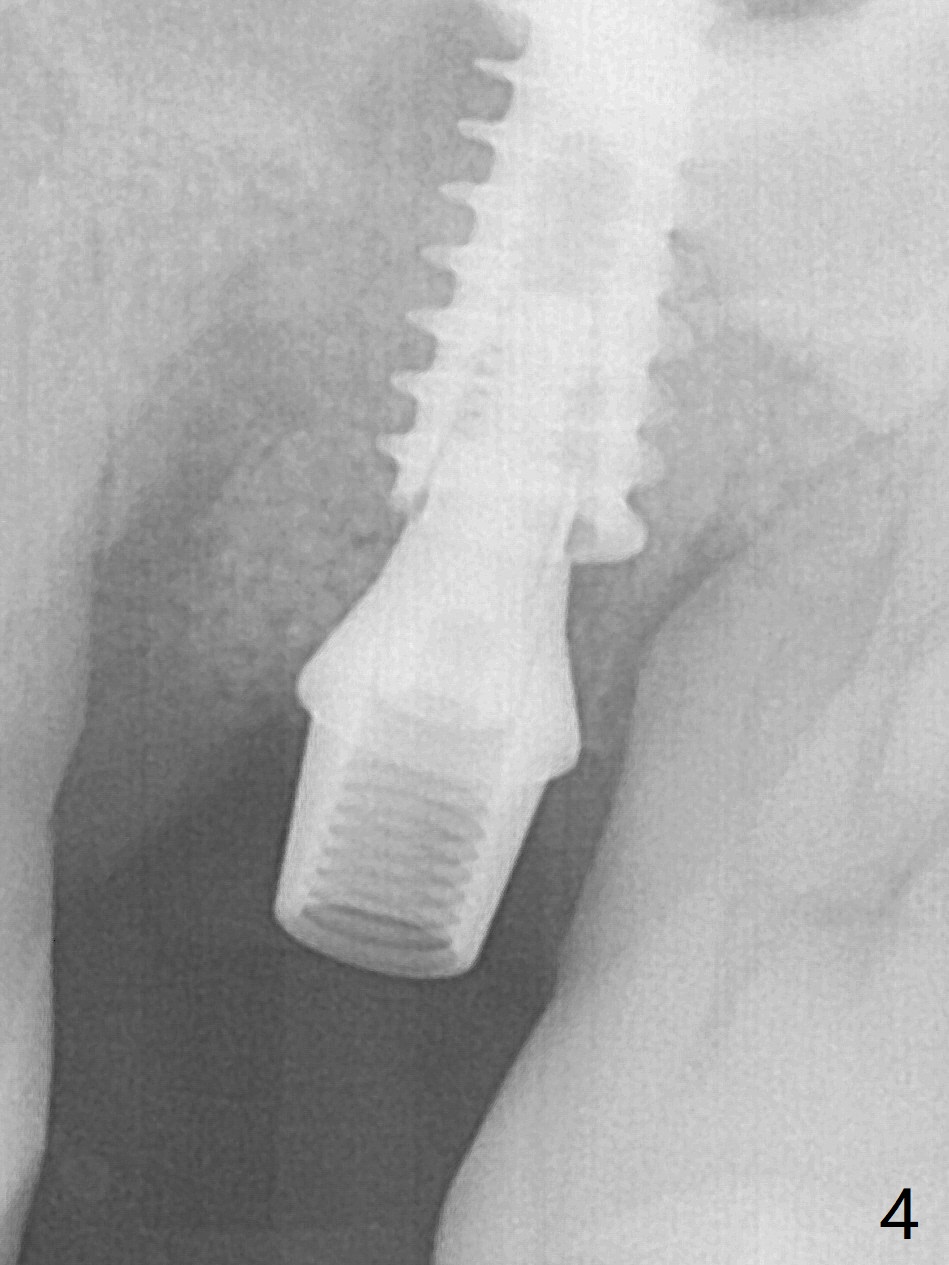

Osteotomy is initiated with Magic Split and 3 mm Magic Expander (ME, flapless) nearly 3 months post socket preservation. To improve the trajectory, the ME is redirected (Fig.1 red line). After use of 3.8 mm ME, Vanilla Graft is placed in the buccal and mesial aspects of the osteotomy. Following reuse of 3 and 3.8 mm MEs, a 4x11 mm dummy implant is inserted with stability (Fig.2 (*: allograft)). More of allograft is placed prior to placement of 5x11 mm IBS implant (Fig.3,4 (~30 Ncm)). The latter is placed palatal. Last the allograft is placed palatal. A 5x4(2) mm abutment is placed to hold periodontal dressing in place. When the ridge is narrow, the implant should be small; 4 mm probably the most appropriate in this case. There is a buccal gap 2 weeks postop (i.e., after dislodgement of periodontal dressing, Fig.5). The implant and abutment appear to be loose ~ 1.5 months postop. The pair abutment is changed to a healing one (5x3mm). The implant seems to be osteotointegrated 3.5 months posotp (Fig.6). Because of the mesial shift of the tooth #15 (Fig.6 arrow (6 months post #14 extraction; anterior open bite)), an angled abutment (5x4mm, 15 degree) is used (Fig.7). Limited orthodontic treatment has to be initiated because the mesially shifted #15 has no occlusal contact mesially (Fig.7 *). A provisional is fabricated with light supra-occlusion. A separator is placed between #14 and 15. Once a space is created in a week, acrylic is added to the distal surface of the provisional and the separator is re-used. In fact the implant is found to be unstable 4.5 months postop (Fig.8,9). The palatal (P) plate is thin and incomplete. The provisional is reduced infraocclusal. Two months the implant remains unstable and is removed.